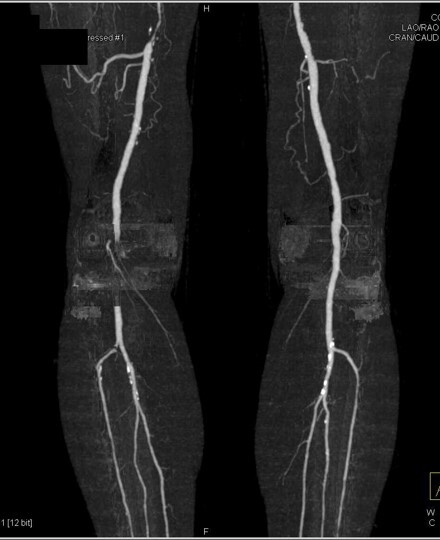

lower extremity vasculature

A

-at the inguinal ligament the external iliac becomes the common femoral artery

-superior, middle, inferior genicular arteries - collateral circulation

-anterior tibial -> dorsalis pedis

How well did you know this?

1

Not at all

2

3

4

5

Perfectly